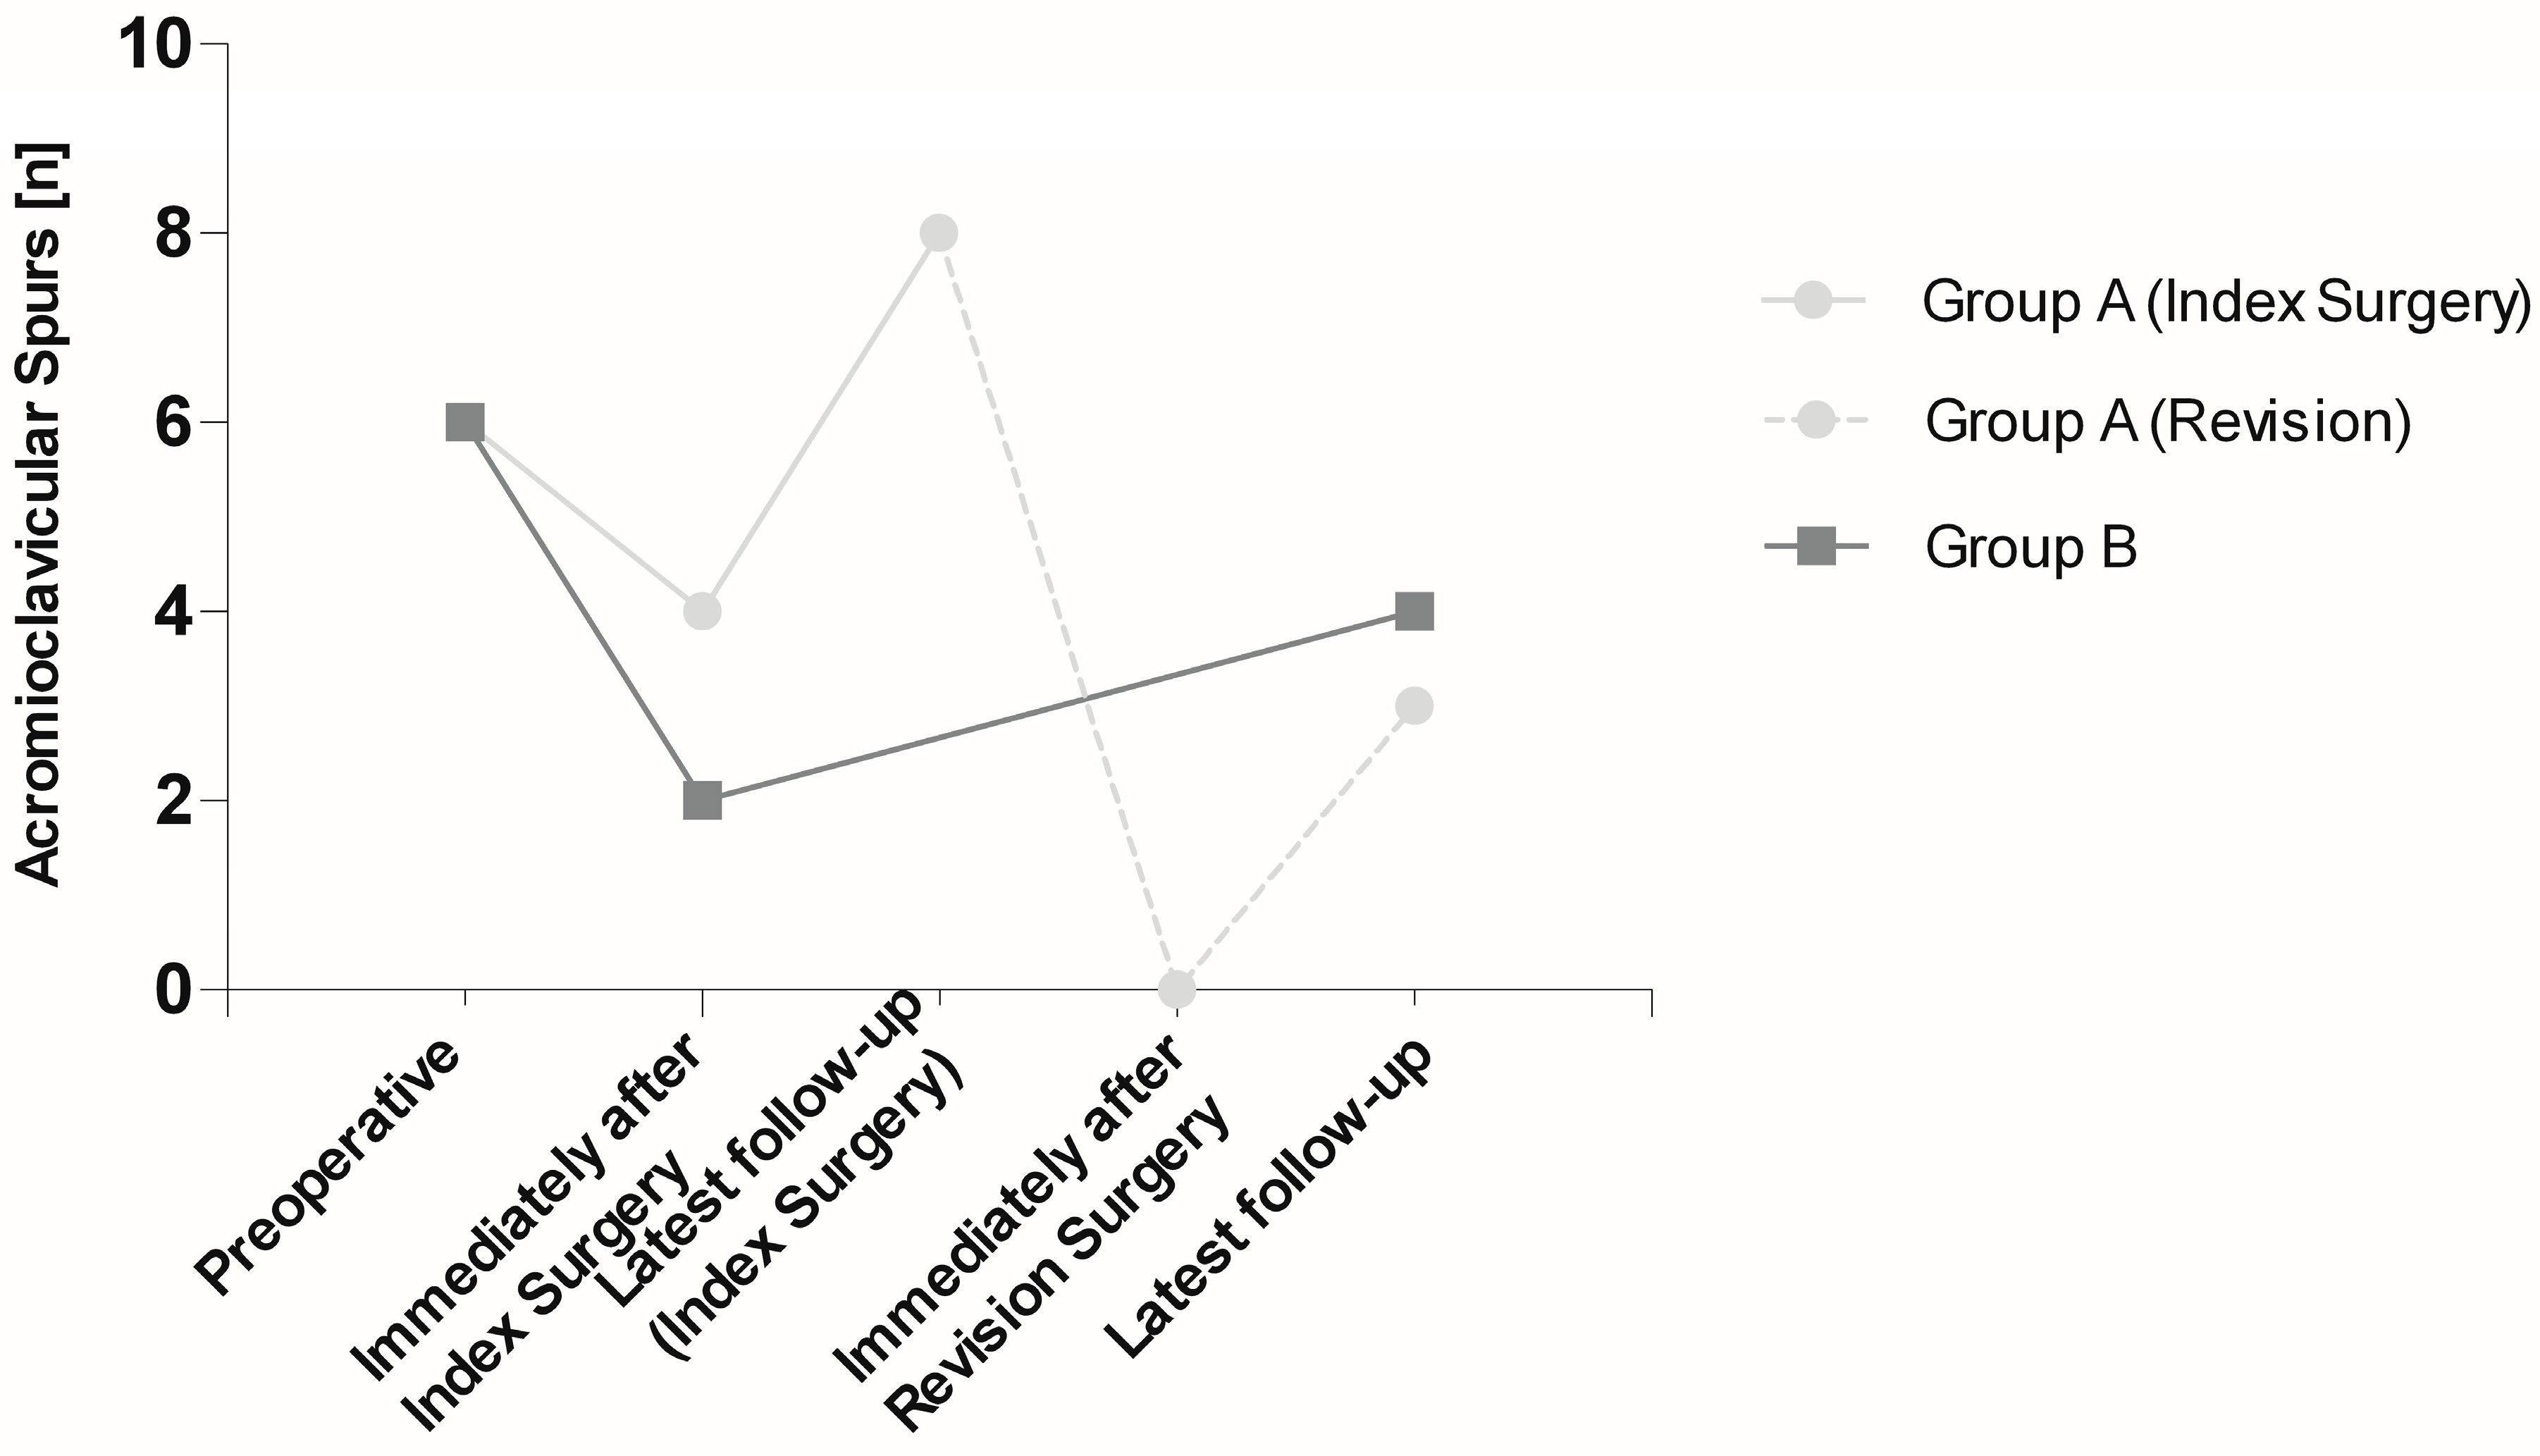

3.1. Radiographic Assessment